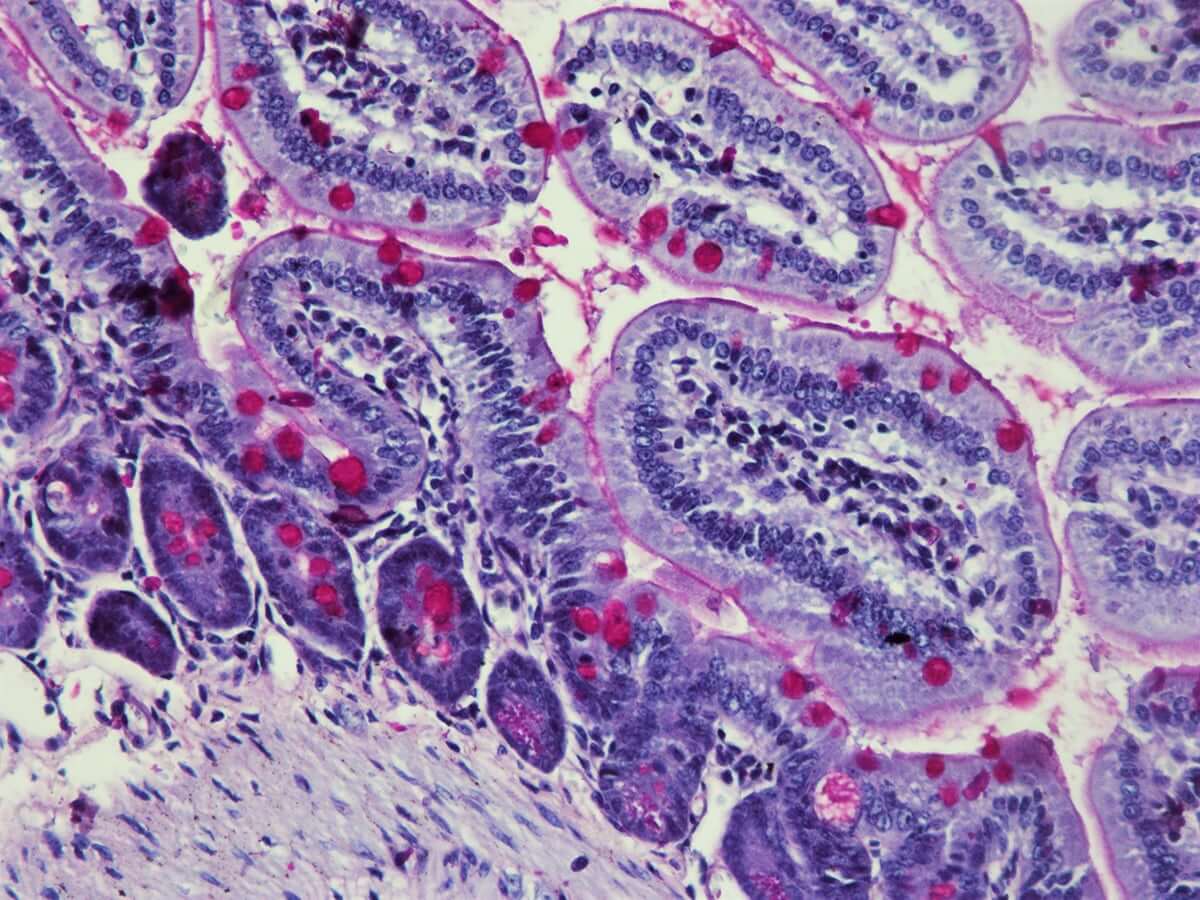

This reagent is used in the staining technique PAS. Periodic Acid Schiff is used to demonstrate simple polysaccharides, neutral muco-polisaccharides, mucoproteins, and glicolipids. It can be used together with hematoxylin or alcian blue.

KH07013_Schiff-Gut-20-x-450x450.jpg

KH07013-Schiff-gut-10x.jpg      KH07013_Schiff-Gut-20-X-2.jpg